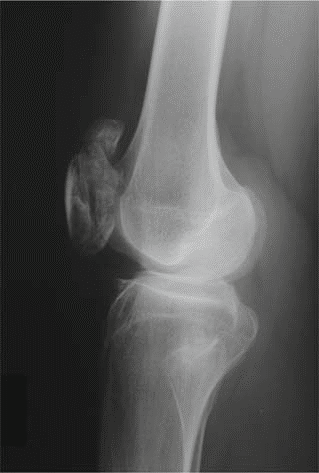

Additional Radiographs (Knees and Ankles):

To assess the widespread nature of MED, radiographs of other commonly affected joints were obtained.

* Knees: Revealed widened and irregular epiphyses of the distal femora and proximal tibiae. Patella alta was noted. Significant joint space narrowing was observed in the patellofemoral and medial tibiofemoral compartments. Mild valgus deformity was confirmed.

* This image typically represents an anteroposterior view of the knee, showcasing the irregular and flattened epiphyses, potentially widened and disorganized growth plates (if skeletally immature), and early degenerative joint changes consistent with the manifestations of Multiple Epiphyseal Dysplasia.